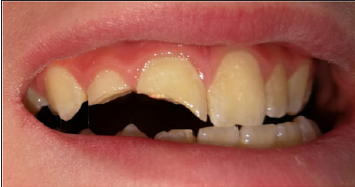

Tooth no.11 was endodontically treated and both teeth were restored. Intra-oral and

radiographic examination revealed an extensive crown fractures of the teeth, involving

enamel and dentin. Both restorations had fallen causing pulp irritation and pain on tooth

no.12, and exposed gutta-percha on tooth no.11 (Figure 1).

Figure 1:The patient on arrival day. Extensive crown fractures due to trauma, and exposed guttapercha on tooth no.11.